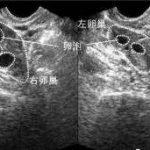

进行试管婴儿手术前,必须要做全面的身体检查。这包括血液检查、输卵管造影、超声波检查等。此外还要进行男方的精液分析和女方的卵巢排卵情况评估等。